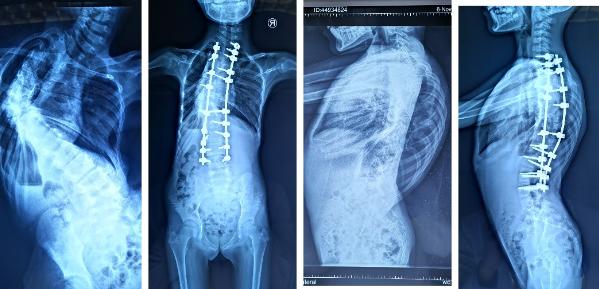

脊柱侧弯手术

脊柱侧弯图片严重图片